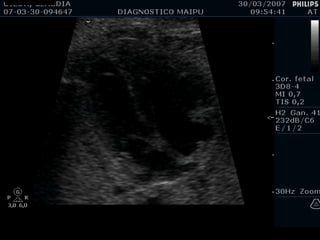

2) LONGITUDINAL / PODALICA / DORSO DER

Apex y estómago: ¿Cerca o lejos del transductor? Long/Pod/D.der Lejos